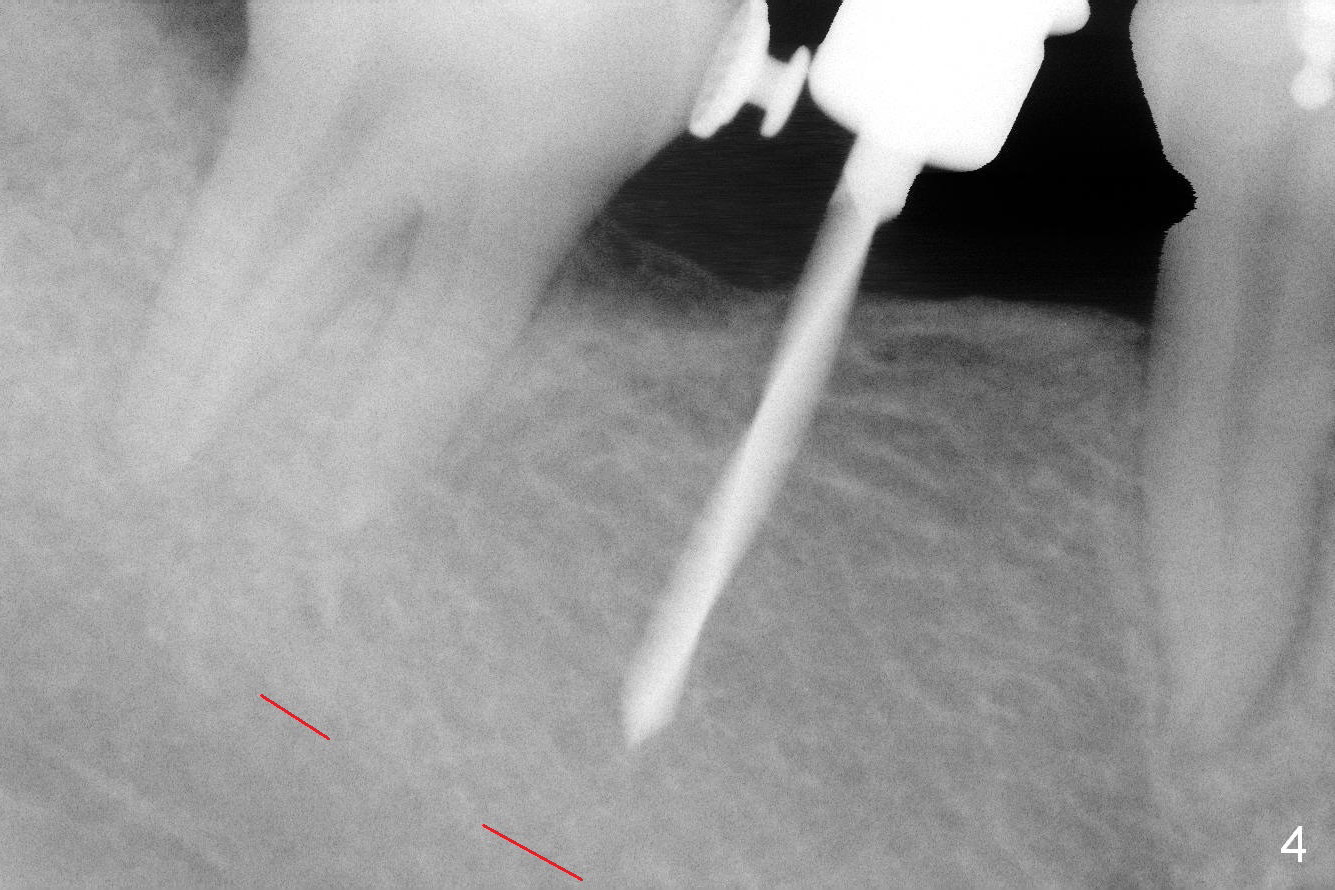

The center of initial osteotomy will be slightly distal (Fig.3 green, parallel to the bicuspid), since more upright will be conducted after implant osteointegration. The initial osteotomy depth will be 11 mm. To place the implant slightly deeper (subcretal), the depth of the last 2nd drill will be 13 mm with stopper. Prior to fabrication of an immediate provisional, place ortho wax around the lingual button of the tooth #31.

The ridge is found to be fairly narrow after incision. Bone density is determined to be high using #15 blade. A 1.6 mm pilot drill is used to initiate osteotomy (Fig.4). The latter is moved mesially. By the time 3.3 mm Magic Drill is in place, the osteotomy is in the better position mesiodistally (Fig.5). The same is a 4x11 mm IBS implant (Fig.6, >55 Ncm). The lingual button in the mesial of #31 is then removed, because it appears to interfere with placement of a 4.5x4(2) abutment. The position of #31 is maintained by open coil spring.